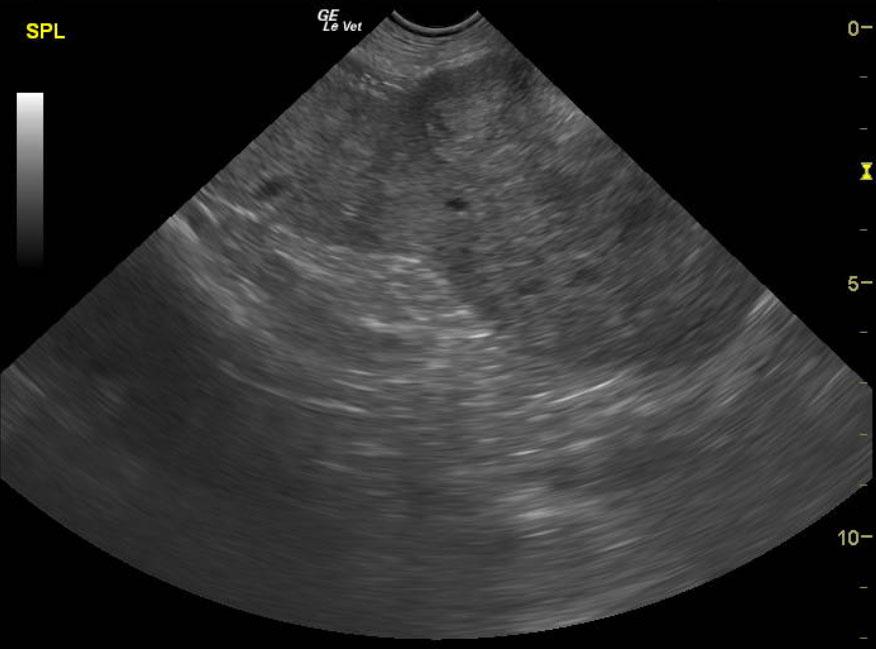

An 11 year old, MN, Rhodesian Ridgeback dog was presented for nonspecific symptoms (ADR). Abdominal mass was palpated. The dog had a subnormal temp (98.8) and pale mucus membranes. Altered CBC/Chem/UA values included leukocytosis, mild azotemia, and mild hypoglobulinemia. Radiographs demonstrated a mass effect in the right abdomen.